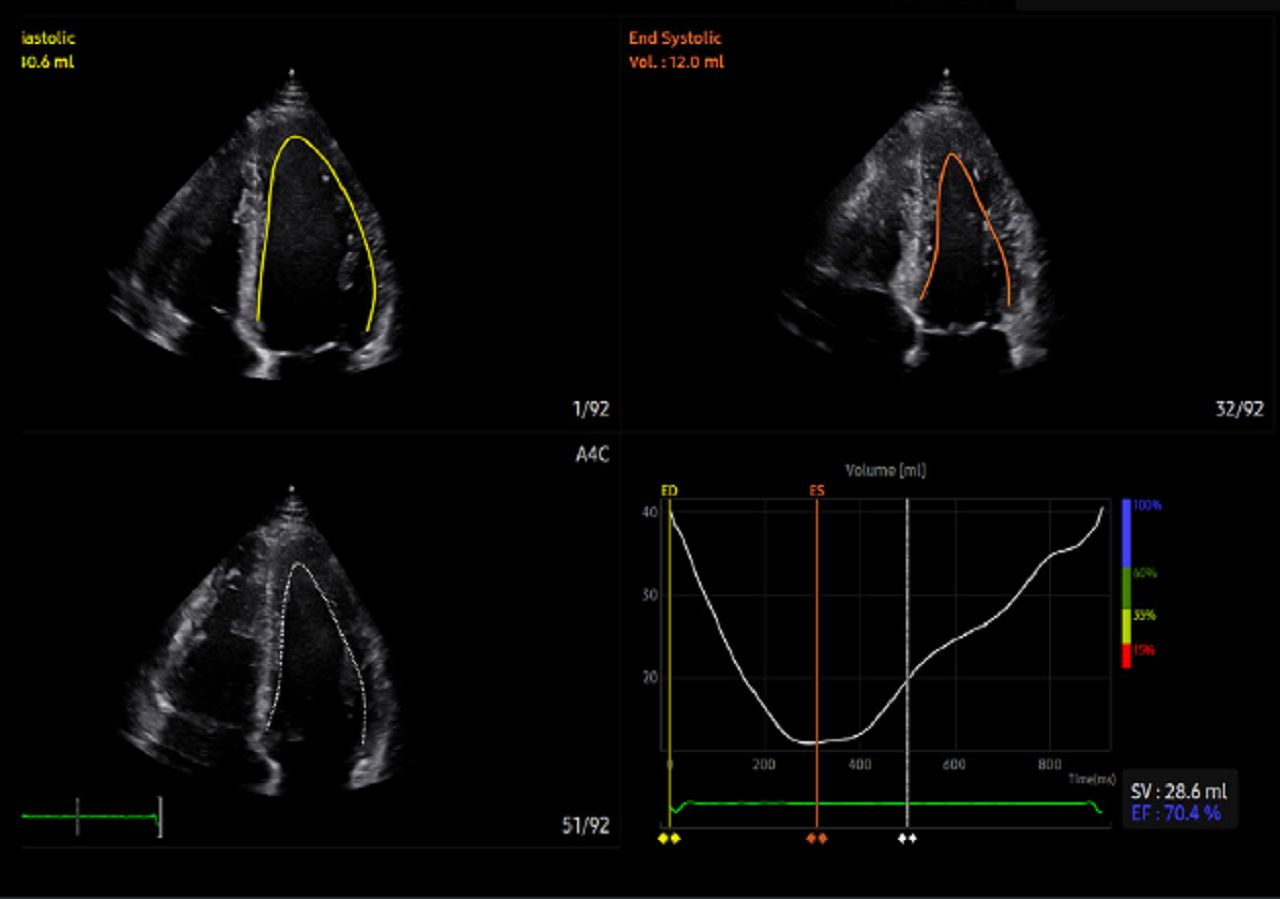

Strain + este un instrument care vă permite să vizualizați și să efectuați o evaluare cantitativă a cineticii peretelui ventricularului stâng (LV). Strain + arată cele trei proiecții standard ale ventriculului stâng și o imagine de tip ochi de taur în format quadscreen, pentru o evaluare ușoară și rapidă a funcției ventriculare.